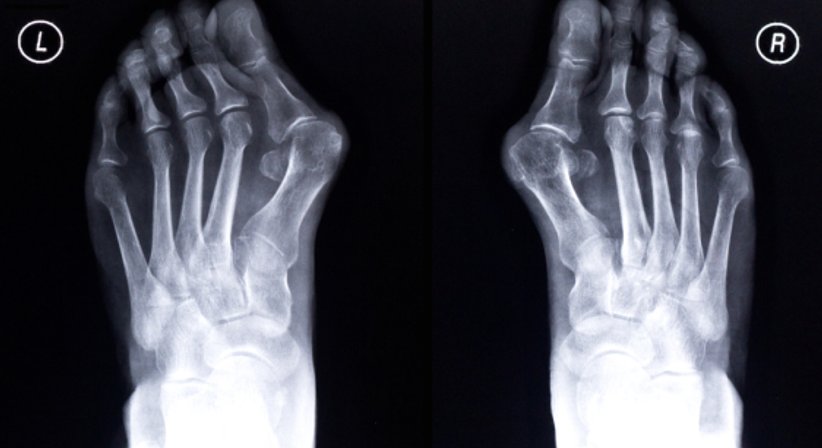

Hallux valgus

Bei einem Hallux valgus handelt es sich um eine Fehlstellung der Großzehe im Grundgelenk nach außen. In vielen Fällen geht die Fehlstellung der Großzehe mit einer Spreizung im Mittelfuß einher. Mit fortschreitendem Verlauf verliert die Großzehe immer mehr an ihrer natürlichen Stellung und winkelt sich in Richtung der anderen Zehen ab. In einigen Fällen kann es passieren, dass die anderen Zehen von der Großzehe "verdrängt" werden. Die Fehlstellung bewirkt, dass sich der Ballenbereich am Innenfuß vorwölbt. Dadurch entsteht die für den Hallux valgus charakteristische und gut tastbare Beule.